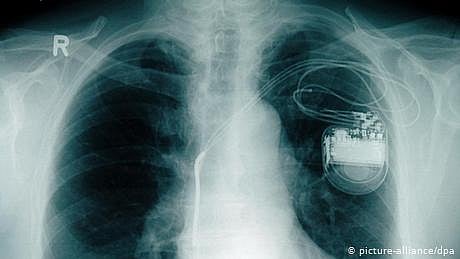

دل کے مریضوں کے لیے نئی امید: بیٹری کے بغیر پہلا پیس میکر